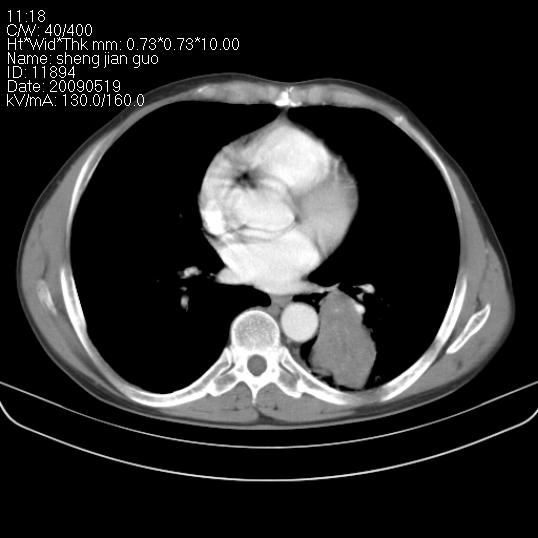

以下是引用zjzjr在2009-5-19 17:25:00的发言:[br]支持楼主考虑,另左肺下叶阻塞性炎症。

以下是引用zhao_bin2008在2009-5-19 17:48:00的发言:[br]支持左肺下叶周围型肺癌并阻塞性肺炎。

以下是引用zsl6918在2009-5-20 7:10:00的发言:[br]左侧中心型肺癌!